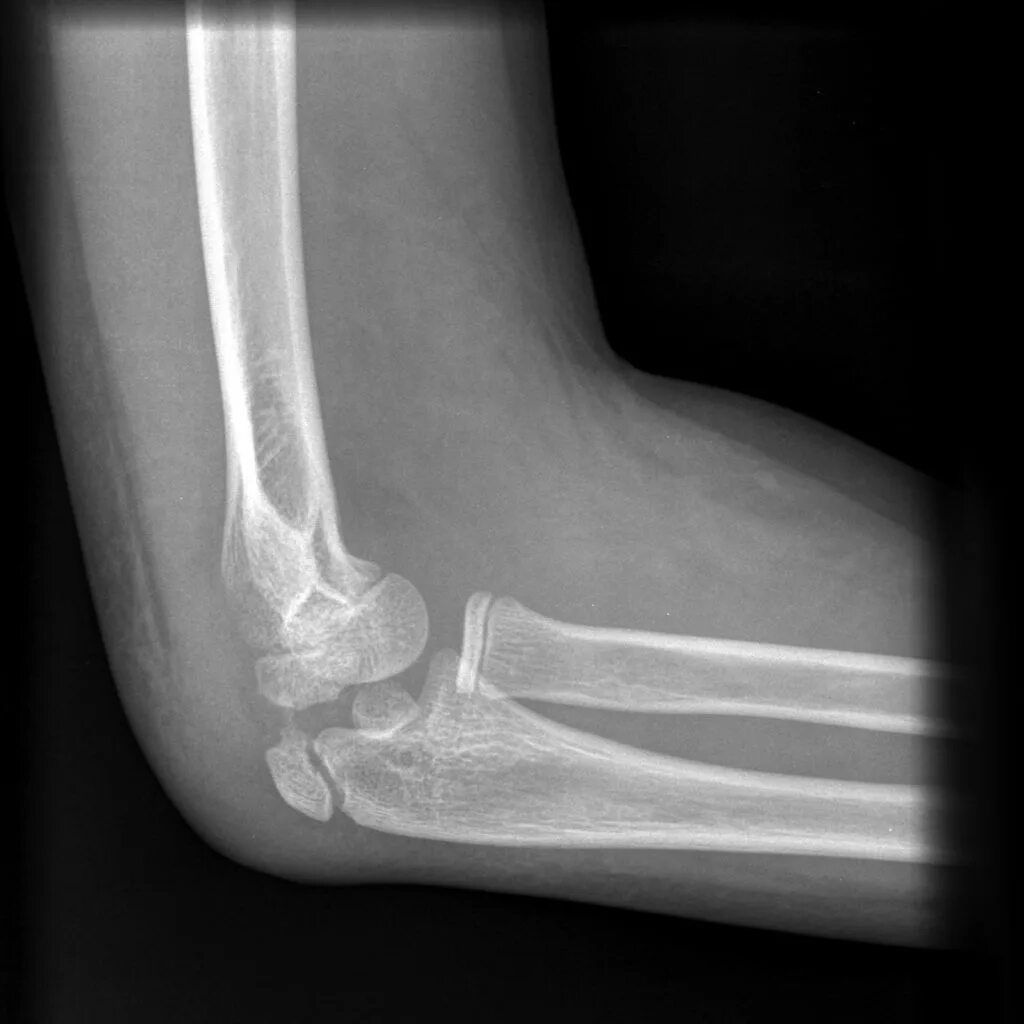

Закрытый оскольчатый перелом со смещением